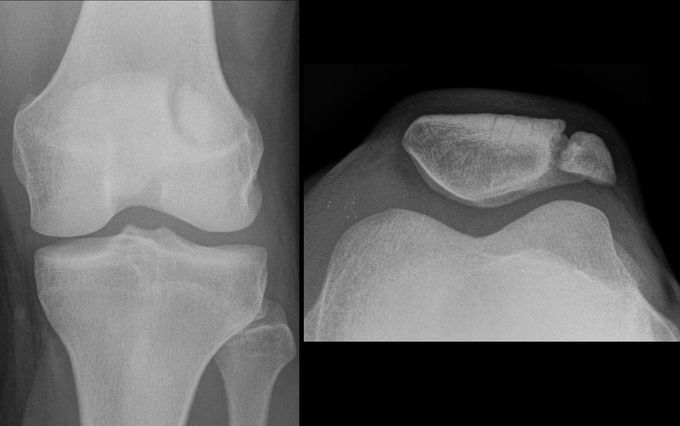

Marieke I have now poster a picture of a fractured patella (latteral view) plus repairment pictures for you to compare :)